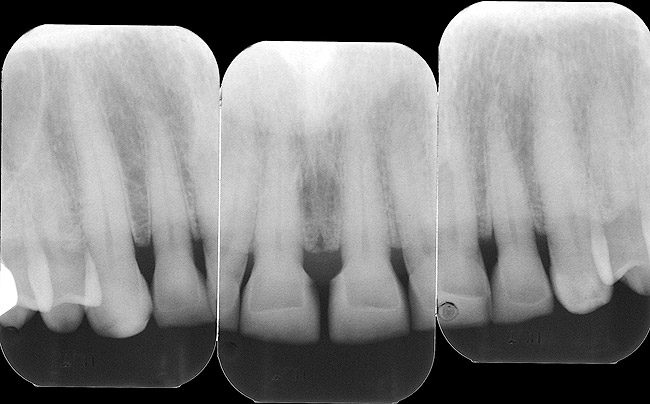

Figure 1a  Clinical situation after the placement of four bonded porcelain restorations (veneer type) on the four vital maxillary incisors, rehabilitating not only esthetics but also function and mechanical integrity of anterior teeth.

Figure 1a

Figure 1b  Preoperative view showing a severe case  of localized erosion and wear with marked and multiple dentin exposures. Such a case is definitely not a contraindication for a conservative approach with bonded porcelain restorations with a facial veneer type IIIB, provided that dentin exposures are sealed immediately after tooth preparation.

Figure 1b

Figure 1c  Clinical view just before the final impression. Note the immediately sealed facial dentin surfaces (smooth texture  of sealed dentin on all four incisors), which is a key element in the long-term success of indirect bonded restorations. The palatal surfaces  were left intact and unprepared.

Figure 1c

Figure 1d  The 1-year follow-up radiographs show perfectly stable situation.

Figure 1d

• i>Maximum tooth structure preservation. When used on full-crown coverage preparations and combined with glass ionomer or modified-resin cements, IDS can result in significantly increased retention, exceeding the cohesive strength of the tooth.29 IDS can therefore constitute a useful tool for improving retention when dealing with short clinical crowns and excessively tapered preparations. Provided that optimal adhesion is achieved also at the inner restoration surface (eg, porcelain etching and silanization, as in the case of inlays, onlays, and veneers), traditional principles of tooth preparation can be omitted and significantly more conservative tooth structure removal is enabled (Figure 1).30